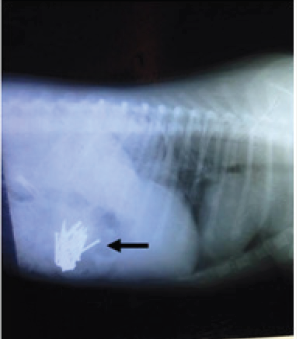

Figure 1: Sagittal reconstructed X-ray image of nails in the left stomach of the dog (black arrows).

An X-ray revealed that most of the nails were in the stomach, with the remaining nails already in the intestines (Figure 1 & 2). The dog was initially treated conservatively with a pain reliever tilidine. According to the results of X-ray, the surgery was immediately operated after an ultrasonography examination, which confirmed the definite nail position.

Figure 2: Sagittal reconstructed X-ray image of nails in the stomach and intestinal tract of the dog (black arrows).